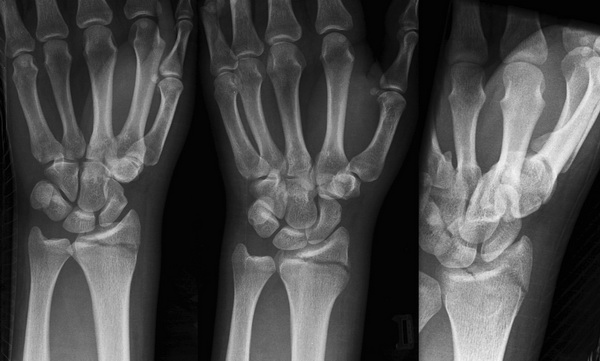

Перед началом лечебных мероприятий необходимо провести диагностику повреждения, и одного визуального осмотра недостаточно. В большинстве случаев достаточно стандартной рентгенографии в двух проекциях. Однако при подозрении на внутрисуставный перелом может потребоваться компьютерная томография. После объективной оценки типа перелома можно переходить к выбору метода лечения, учитывая возраст и уровень активности пациента.